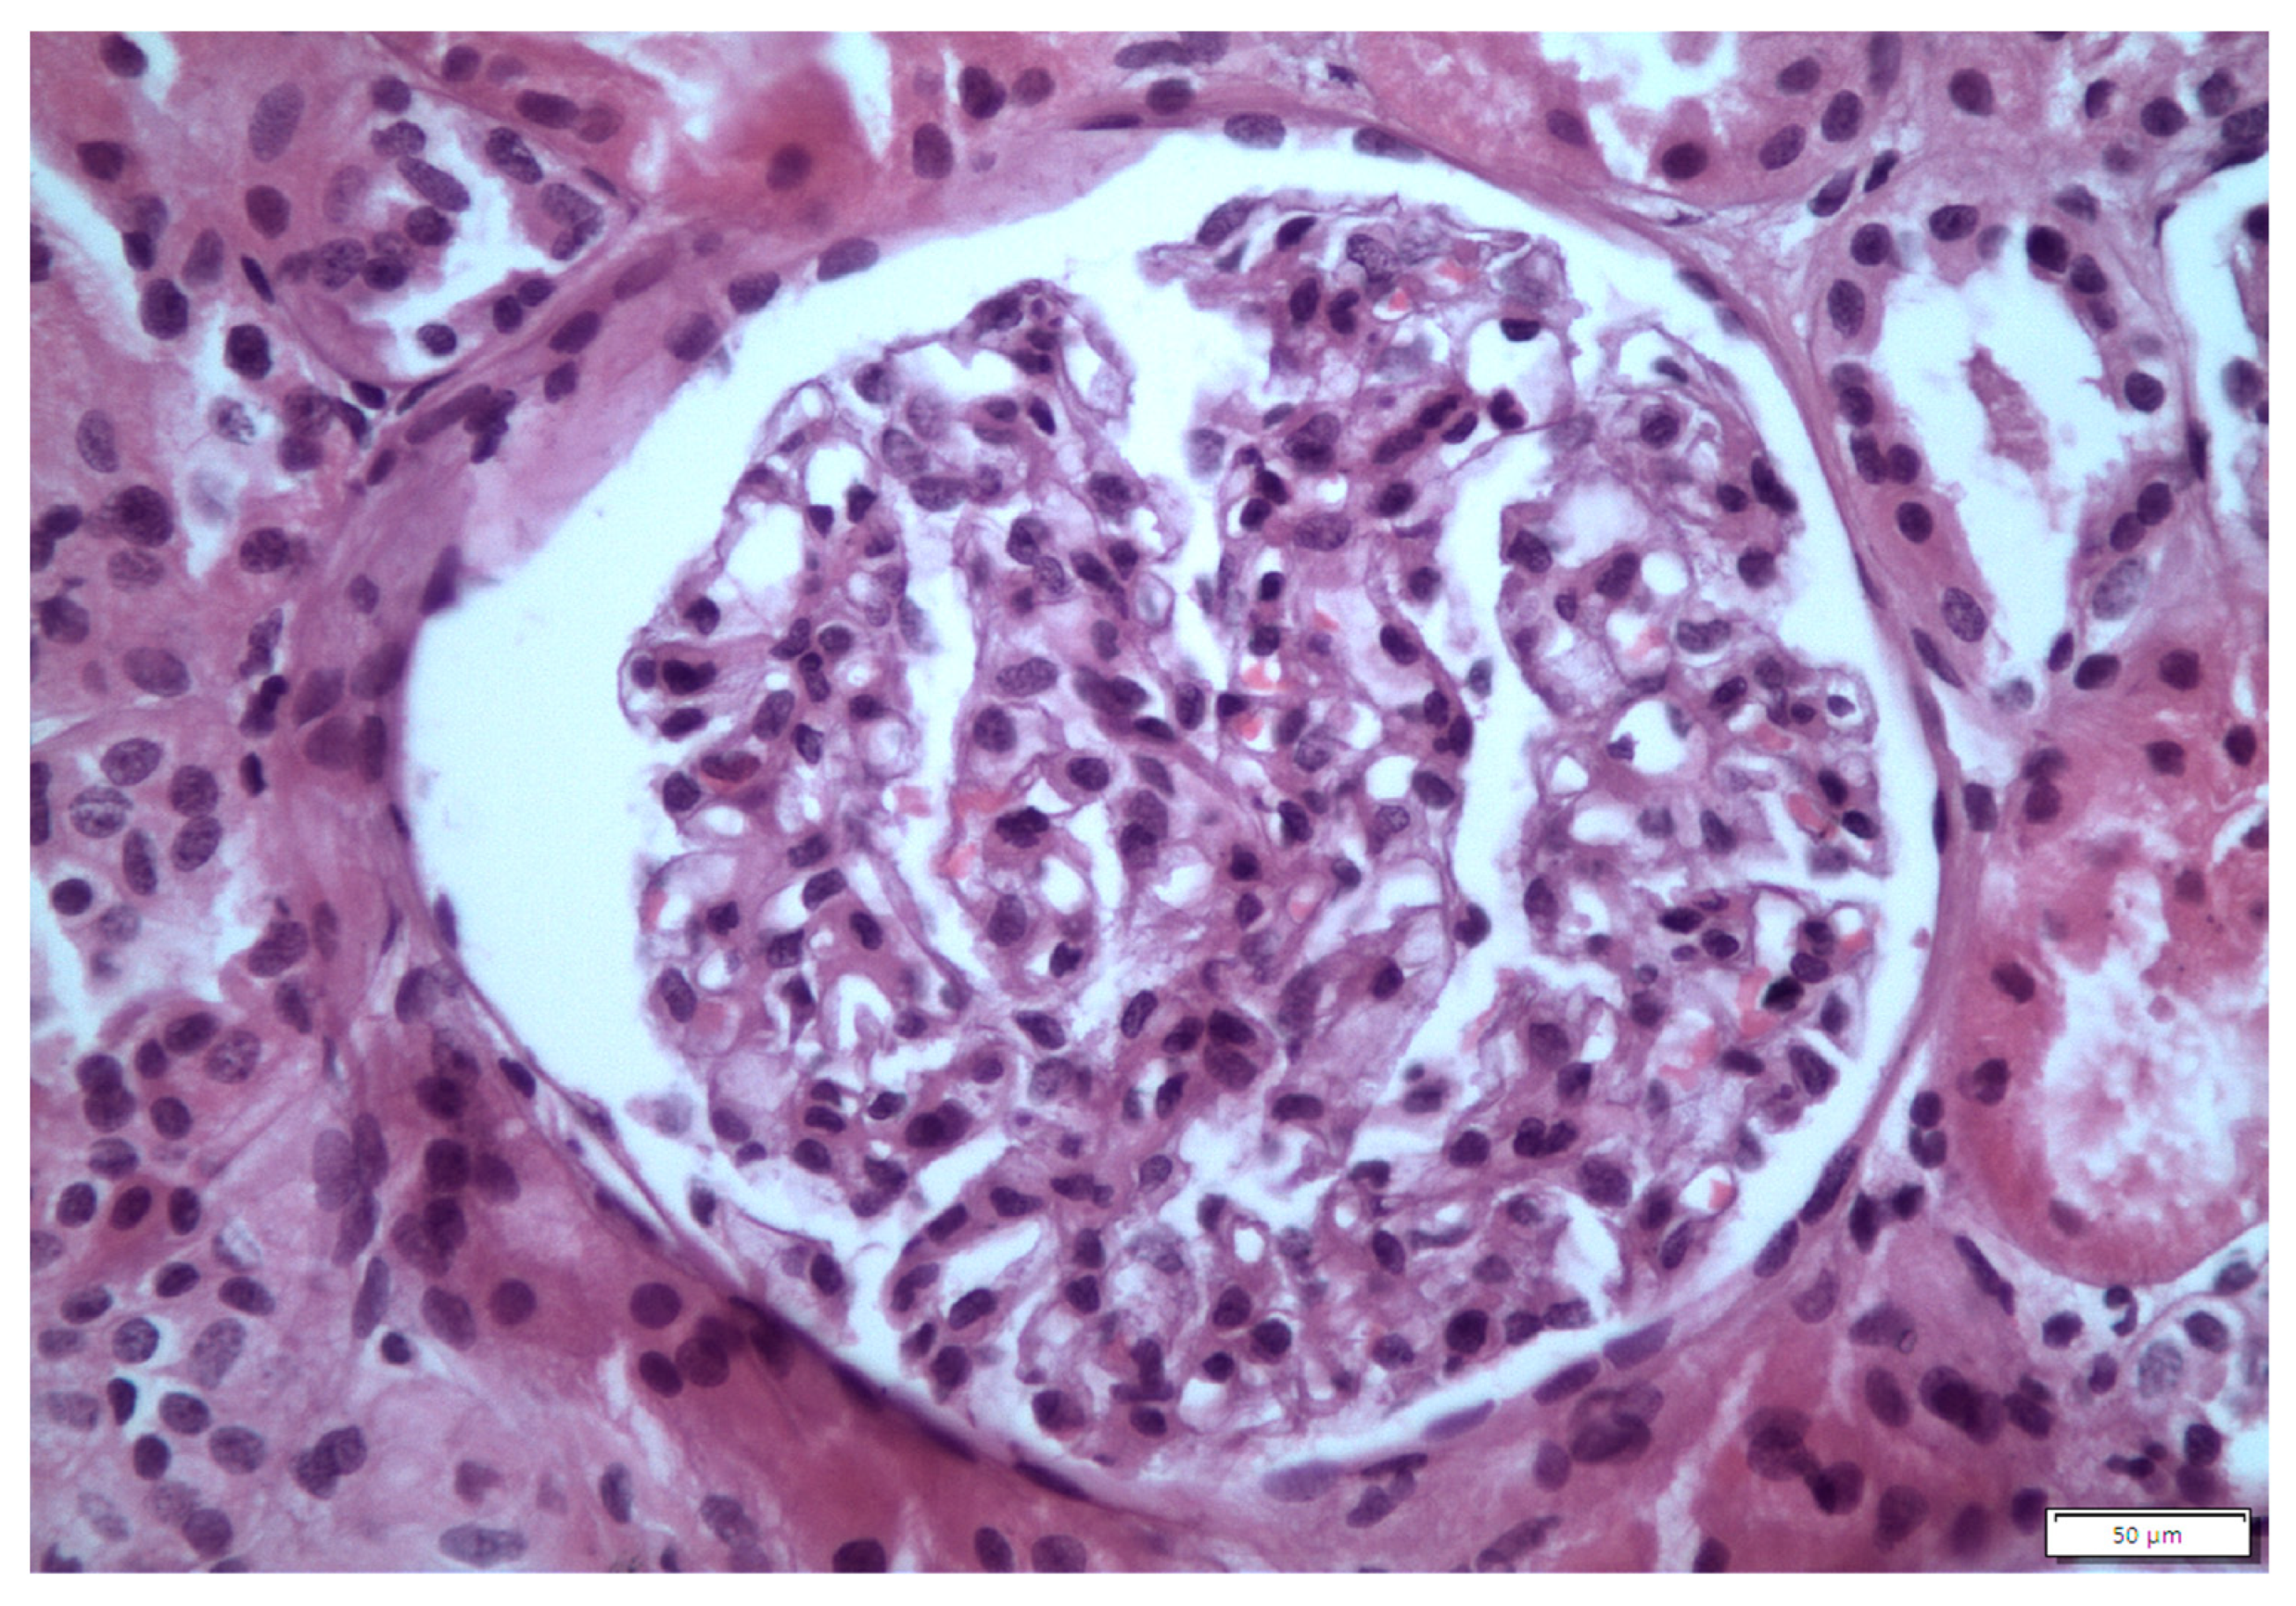

2. Case 1 Description: MCD Associated with Tamoxifen

3. Case 2 Description: MCD Associated with D-Penicillamine

4. Case 3 Description: D-Penicillamine-Associated MCD

5. Case 4 Description: Pembrolizumab-Axitinib-Induced MCD